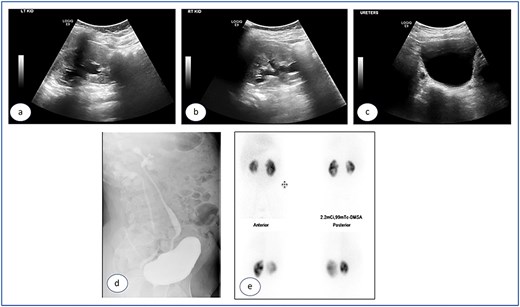

A 7-year-old child was referred to the pediatric urology clinic due to a history of recurrent febrile urinary tract infections and urge incontinence, accompanied by constipation (Bristol 2). These symptoms persisted despite meticulous conservative management, including urotherapy. Ultrasound (US) revealed bilateral pelviectasis and voiding cystourethrogram (VCUG) revealed bilateral Grade 3 VUR and a mildly trabeculated bladder wall, whereas the urethra appeared normal (Fig. 1a–d). A DMSA renal scan verified bilateral renal scarring, revealing differential renal function of 40% in the right kidney and 60% in the left kidney (Fig. 1e). Endoscopic intervention was warranted, and 1 ml of Deflux was injected on the left side and 0.6 ml on the right side, successfully creating an adequate mound. The patient was discharged in stable condition for several hours following surgery, despite being anuric. Subsequently, the patient experienced intense abdominal pain and was admitted to the emergency department. The physical examination was uneventful, except for moderate hypertension. The urinalysis revealed microscopic hematuria. His urea level was 16 mmol/L, and creatinine rose to 126 umol/L from a baseline of 40 umol/L. Post operative US at emergency room demonstrated increased bilateral hydronephrosis (Fig. 2).

Post Deflux injection ultrasound images showing the left (a), and right (b) kidneys and the urinary bladder (c).